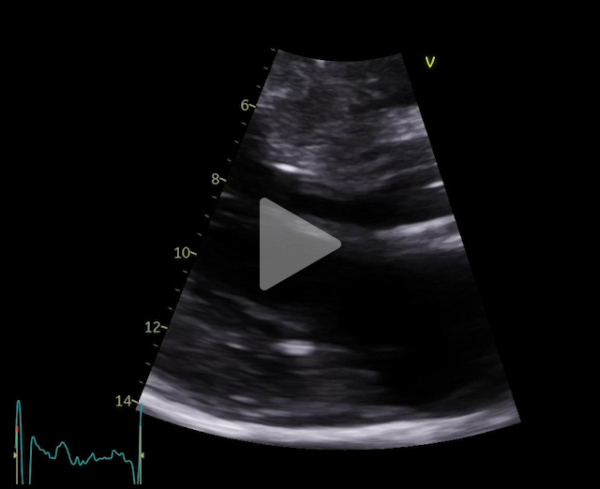

Voici son échocardiographie

Vidéo 3 : échocardiographie 2D en incidence parasternale grand axe zoomée sur la valve mitrale